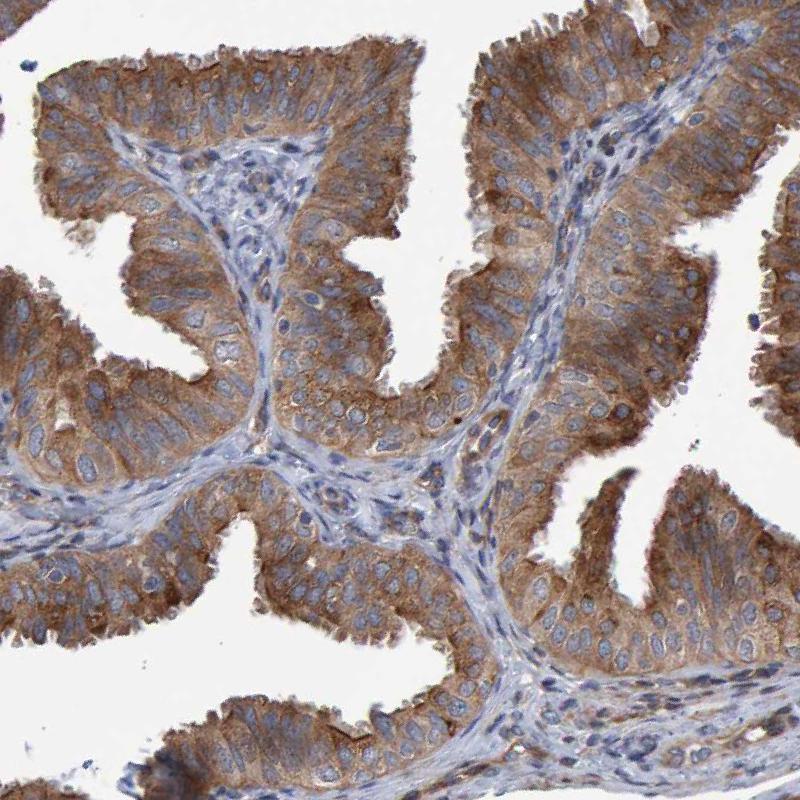

Immunohistochemical staining of human rectum shows strong cytoplasmic positivity in glandular cells.